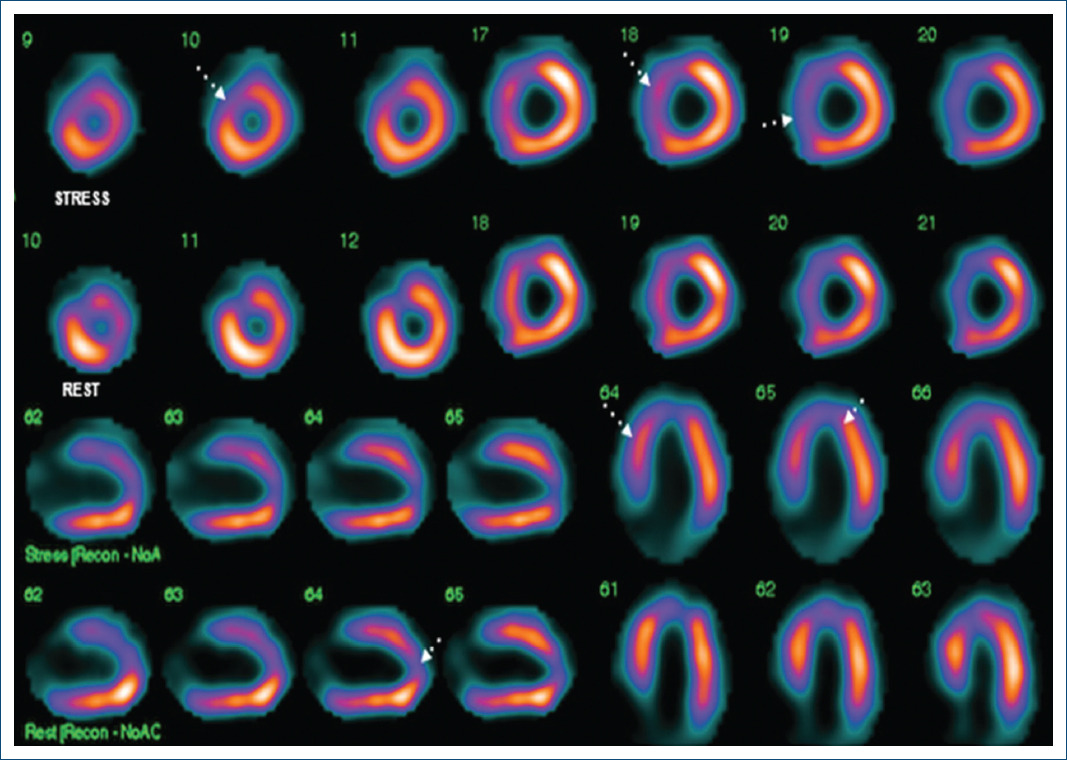

Figure 1 Protocol stress-rest with 99mTc-methoxy-isobutyl-isonitrile (99mTc-MIBI) myocardial perfusion SPECT images pre-operative of the short-axis slices, horizontal, and vertical long axis. The images show a defect in the apex, apical anterior, and septal wall, which during stress increases the defect. Non-transmural infarction of the apex and anteroapical with mild ischemia.

In addition, significant angulation of the left main coronary artery and LAD and dilation of the left chambers were noted by the study. Protocol stress-rest with 99mTc-methoxy-isobutyl-isonitrile (99mTc-MIBI) myocardial perfusion SPECT showed anteroseptal and apical non-transmural infarction with mild residual ischemia (Fig. 2). Surgical correction with reimplantation of the LCA to the aorta was performed. The procedure was uneventful, there were no post-operative complications, and the patient fully recovered. The patient has been asymptomatic since the surgical procedure. Cardiac MRI after the procedure showed post-surgical reimplantation of the left main coronary artery to the aorta, no significant changes in the other cardiac structures were noted.

Clinical presentation can range from sudden death at birth, to dyspnea, pallor, and failure to thrive in infants. Adults present with chest pain, angina, syncope, heart failure, or sudden death. Adults who develop heterocoronary collateral vessels can be asymptomatic. In the absence of collateral circulation, mortality is approximately 90% without prompt diagnosis and surgical repair2,4. Perfusion of the anterior wall depends on the collateral circulation of the RCA. This can cause perfusion defects leading to ischemia. In fact, our patient presented with a non-transmural infarction of the anteroseptal and apical wall5.